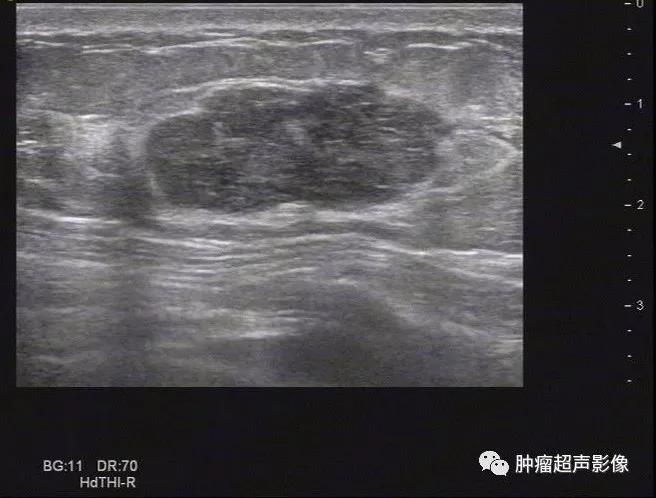

良性叶状肿瘤: 女,51,边界清,假包膜,条索状高回声,血流少许,结合年龄及肿块表现需要考虑叶状肿瘤。